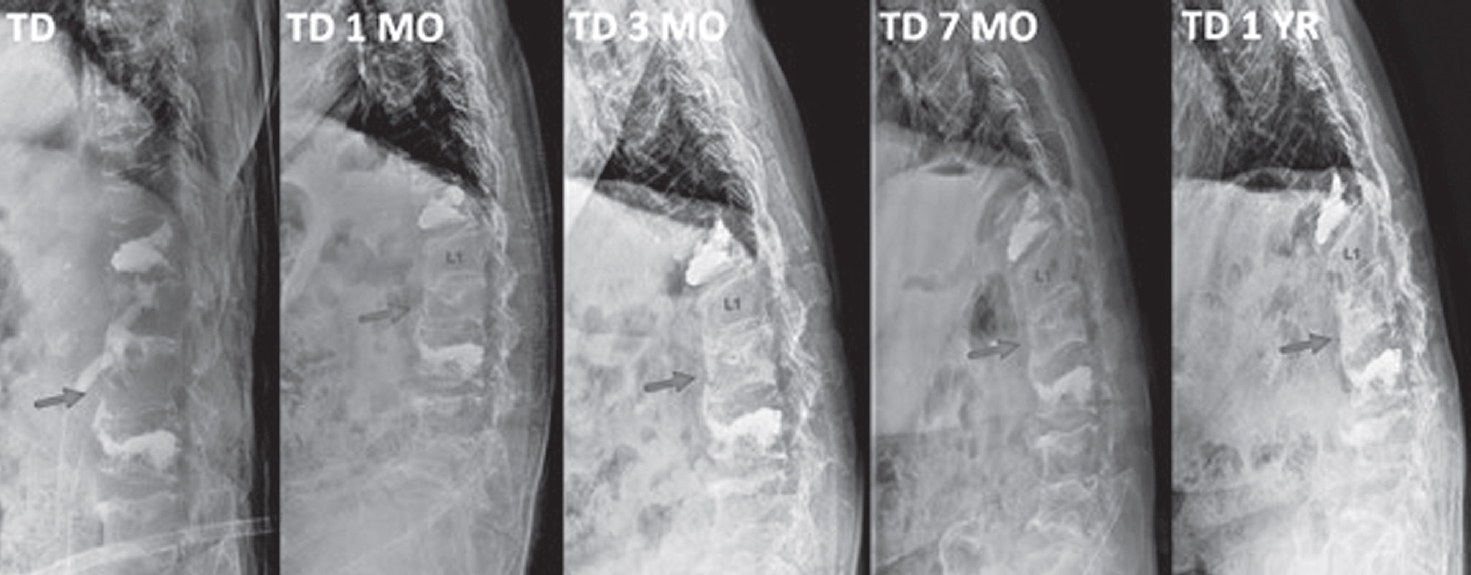

An 85-year-old woman presented with acute back pain after falling on an escalator. Neurological examination showed no motor or sensory deficits and no bowel or bladder dysfunction. Her medical history included vertebroplasty for T12 and L3 compression fractures and a right subtrochanteric femoral fracture treated with plate fixation. After the femoral fracture surgery, she had received intravenous bisphosphonate therapy at 3-month intervals for two years. Initial radiographs revealed multiple chronic vertebral compression fractures, and computed tomography identified a new L2 compression fracture (Fig. 1).

Fig. 1.

Initial lumbar spine anteroposterior and lateral radiographs demonstrating an acute L2 compression fracture and multiple chronic compression fractures and prior vertebroplasty at T12, L3.

Fig. 1. Initial lumbar spine anteroposterior and lateral radiographs demonstrating an acute L2 compression fracture and multiple chronic compression fractures and prior vertebroplasty at T12, L3.